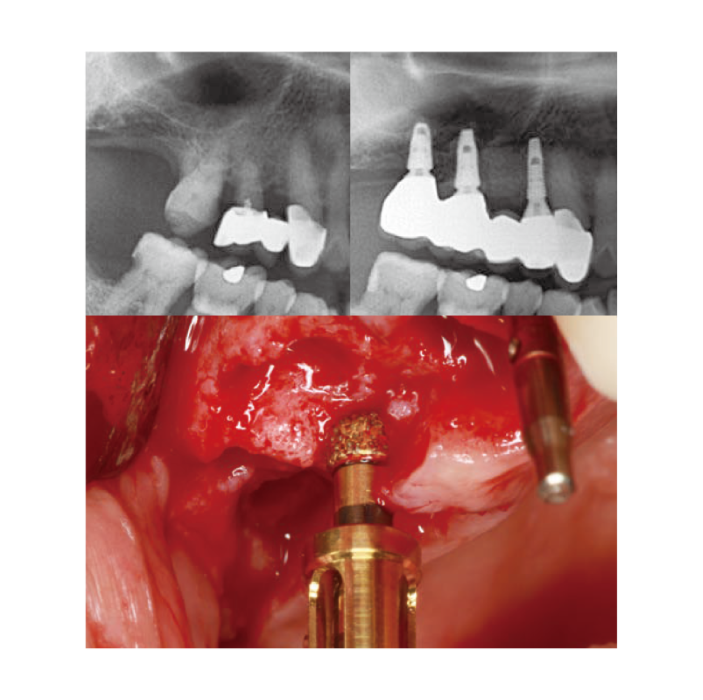

Crestal Approach

Crestal Approach -